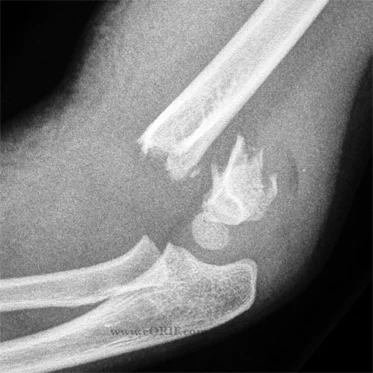

Causes

-

Hematoma

- Fracture hematoma

- Soft tissue trauma

- Arterial injury

- Bleeding disorders - hemophelia**